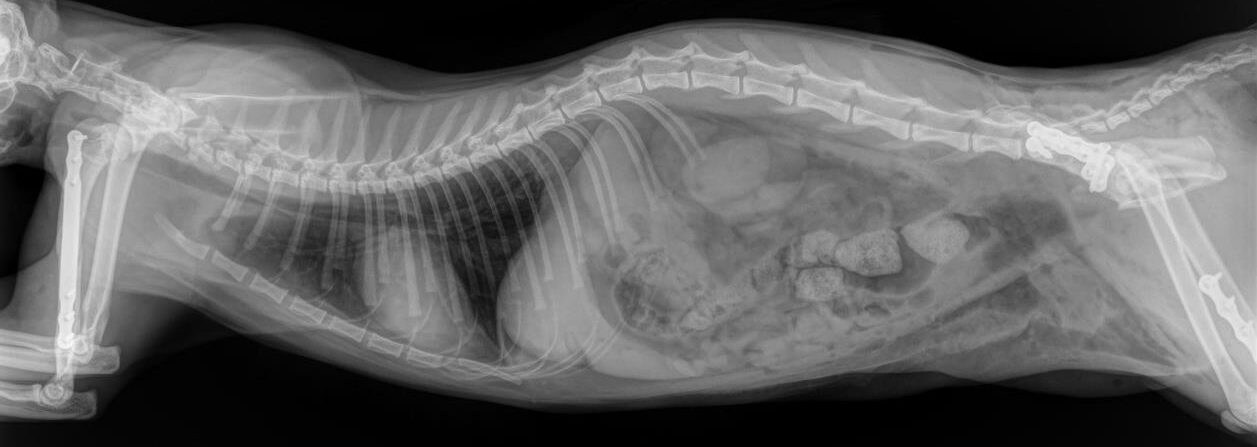

Our client Dr. Sonntag recently wrote us an email with the subject: Here’s why they changed the name of their cat to “LeiLOX”. With this email, he sent us a ton of x-rays - all of which were taken from a single cat patient.

Her owner traversed her with her car thinking it was a sack of flower soil. Sick at heart and believing her cat is going to die, but not giving up hope, the owner brought her to the animal clinic. (Spoiler alert: Dr. Sonntag bought a full LeiLOX kit 5 days before). Can you imagine what Dr. Sonntag was going to expect?

Day 1: He had to fix a humerus spiral fracture (left) with a LeiLOX bridge plate. Furthermore, he diagnosed a femur transverse fracture. Dr. Sonntag then used a 7-hole LeiLOX plate to repair this fracture, and do several emergency soft tissue surgeries.

Day 2: Repair of two iliac bone traverse fractures (left and right) with LeiLOX L-plates. Finally, several soft tissue surgeries were performed.